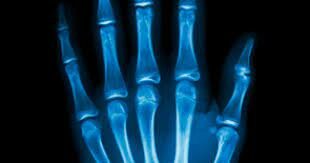

• Descubrimiento rayos x

Descubrimiento rayos x

el físico alemán Wilhelm Conrad Roentgen descubrió los rayos X mientras realizaba experimentos con tubos de vacío y un generador eléctrico. Con el hallazgo de este haz de luz capaz de atravesar la materia, nació el diagnóstico médico por imágenes que mejoró considerablemente el ejercicio de la medicina.